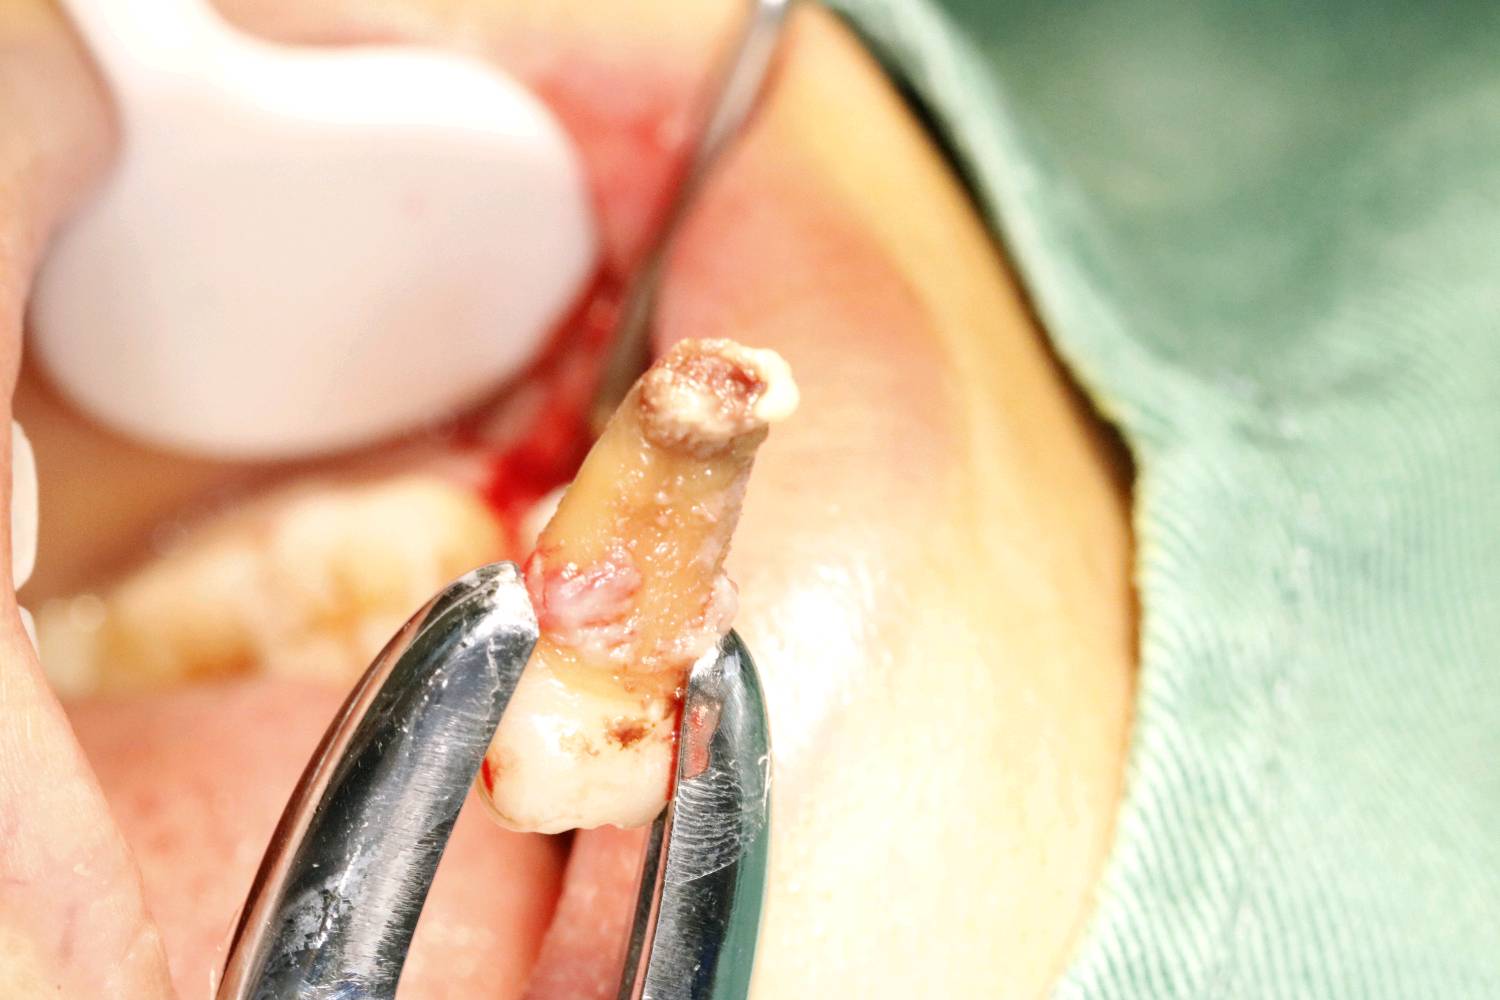

畸形中央尖多发生于下颌第二前磨牙,是一种牙体形态的发育异常,畸形中央尖本身不是什么大问题,只是折断或者磨穿了才会有不好的后果。这位患者就是因为没有长期的磨耗使的根尖周发生炎症时,导致根尖发育停止,根管口呈喇叭口状。对于这种牙根过短,根尖炎症范围过大的患牙,则考虑给予拔除。拔出后植入骨粉骨膜,后期种植修复。

术中